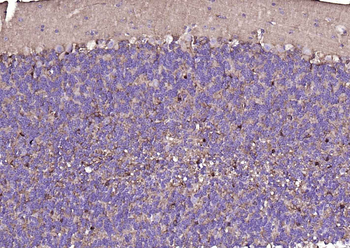

CD56 Antibody

Catalog Number: orb1317086

| Tested applications | IHC, WB |

| Reactivity | Human, Mouse, Rat |

| Dilution range | WB 1:2000, IHC 1:150 |